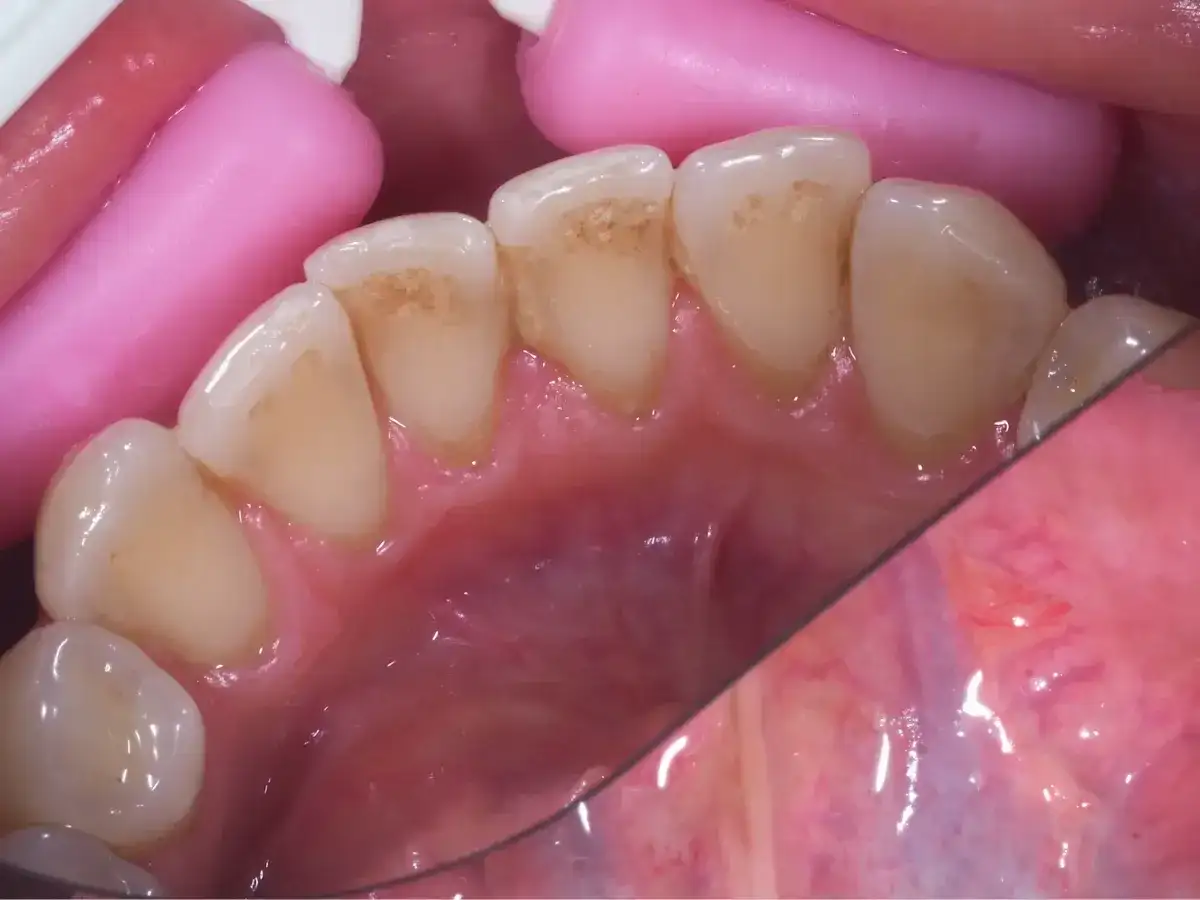

Jak wygląda kamień na zębach? Objawy i skutki zdrowotne

Dowiedz się, jak wygląda kamień na zębach, jakie są jego objawy oraz skutki zdrowotne. Zadbaj o zdrowie jamy ustnej i unikaj problemów!